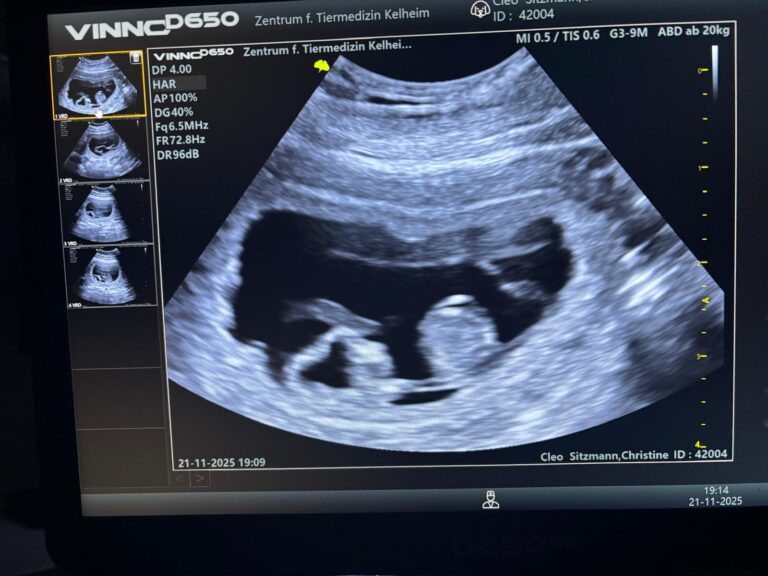

Cleopatra wurde am 23.10.25 von King Kilfane vom Märchenmond gedeckt.

Ende November gehen wir zum Ultraschall und dann wissen wir ob das Date Früchte getragen hat.